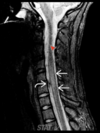

We can see lesions in the spinal cord in patients who have multiple sclerosis. Where is the most common location these lesions occur? 1 - cervical 2 - thoracic 3 - lumbar 4 - sacral

1 - cervical

42

Transverse myelitis is a neurological inflammatory disorder that affects both halves of the spinal cord. What is a typically sign on an MRI that can help diagnose transverse myelitis? 1 - detached spinal cord 2 - central expansion of the cord over more than 2 vertebrae 3 - lesions across the full width of the spinal cord 4 - lesions at the junction with the brain stem

2 - central expansion of the cord over more than 2 vertebrae - 2/3 of patients are left with some form of disability